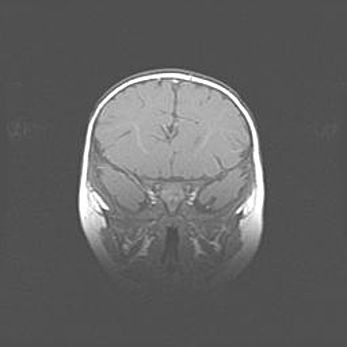

Наружная гидроцефалия с возможной атрофией височных областей.

Возраст: 28 дней

Вес: 3670 г

Пол: мужской

Окружность головы: 38 см

Срок гестации: 40 недель

Гидроцефалия головного мозга у новорожденных – это заболевание, которое характеризуется скоплением избыточного количества спинномозговой жидкости в желудочковой системе головного мозга в результате затруднения её перемещения от места выработки к месту поглощения в кровеносную систему или вследствие нарушения абсорбции. При открытой наружной форме гидроцефалии у новорожденных расширяются и переполняются субарахноидные пространства.

При нормотензивных  формах,  которые,  как  правило,  являются  следствием  перенесенных ишемических  повреждений  паренхимы  мозга,  возможно  сочетание микроцефалии  с нормотензивной гидроцефалией. В основе данных изменений лежит атрофия больших полушарий с преимущественной  локализацией  в  лобно-височных  областях.